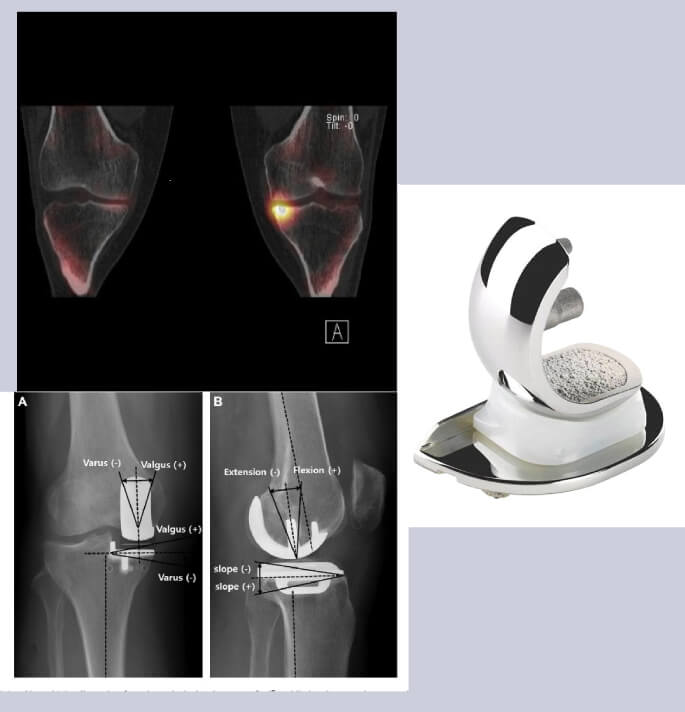

Artrose kan zich beperken tot één compartiment van het gewricht (unicompartimenteel mediaal, lateraal of patellofemoraal) of kan zich uitbreiden over het hele gewricht.

Bij unicompartimentele variserende slijtage mediaal wordt, mede ook afhankelijk van de leeftijd van patiënt, een valgiserende tibiale osteotomie (correctie van de as van het been) of een mediale unicompartimentele knie artroplastie (halve knie) voorgesteld.

Bij ernstige knieschijf/knieschijf goot (patellofemorale) artrose kan een patellofemorale prothese baat vol zijn.

Globaal zijn er 2 belangrijke technieken voor het plaatsen van een totale knieartroplastie.

De ” gemeten resectie techniek” (measured resection) waarbij hoofdzakelijk rekening wordt gehouden met de beenderige contouren en assen van het been (ook robots maken hoofdzakelijk

gebruik van deze techniek) of

De “gebalanceerde resectie techniek” (balanced resection) waarbij het plaatsen van de prothese mede begeleid wordt door de correcte spanning van deomliggende weke delen (ligamenten pezen en spieren). Het zijn deze weke delen welke in de postoperatieve fase een goede stabiliteit en mobiliteit zullen bewerkstelligen. Het belang van deze laatste techniek werd bevestigd door de informatie die we verkregen bij het gebruik van de E-lbra balancer welke door ons werd ontwikkeld.